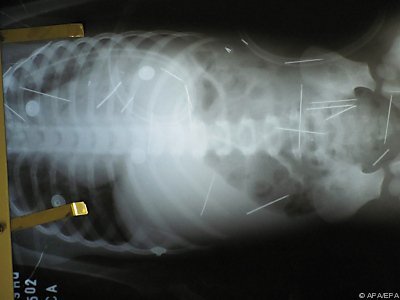

Brasilien: 50 Nadeln im Körper von Zweijährigen